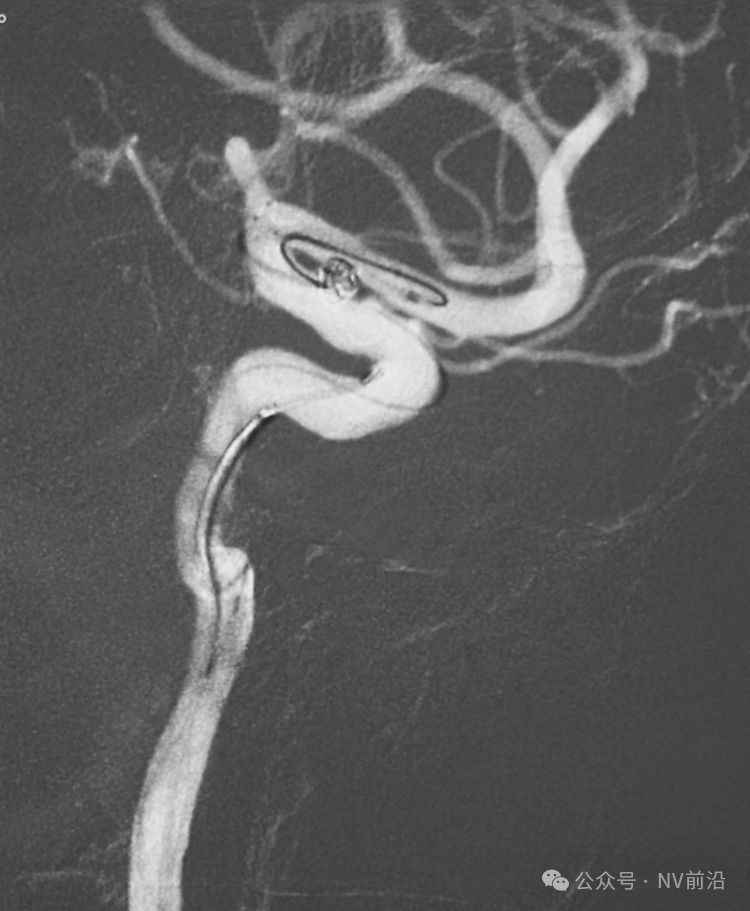

术后左颈内动脉工作位造影和蒙片。

术后左颈内动脉造影三维重建显示动脉瘤消失。

术后右椎动脉工作位造影,

以及正位造影显示动脉瘤完全栓塞,载瘤动脉畅通。